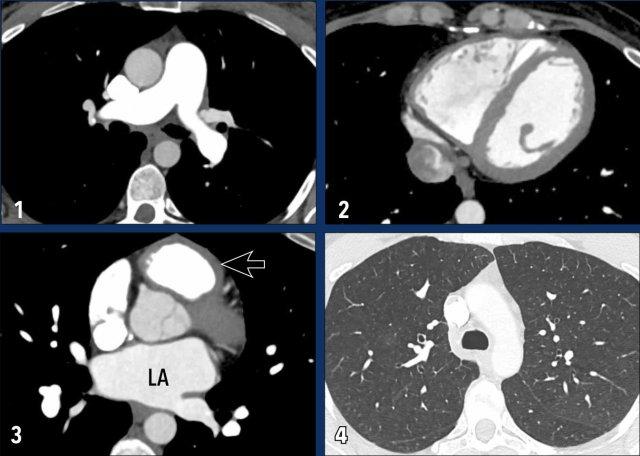

Hình ảnh

Ở bệnh nhân này với bệnh tim trái, các dấu hiệu bao gồm:

- Giãn động mạch phổi chính.

- Giãn nhĩ phải và dày nhẹ cơ tim thất phải.

- Giãn nhĩ trái.

- Tràn dịch màng phổi (mũi tên trắng).

- Dày vách liên tiểu thùy dạng trơn nhẵn (mũi tên đen).